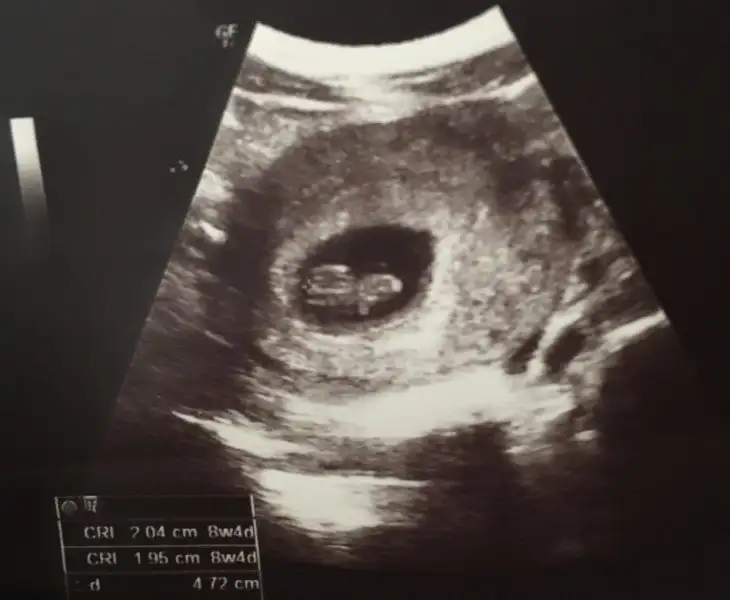

Karından canımPlasenta sağda bebiste saga doğru gidiyor.usg karındansa kız gibi,vajinalsa erkek gibi

Ben fotoyu 16 haftalık sandım:) bebisin kız gibi

Enemm vajinal ikisi deUsg karındansa kız gibi,vajinalsa erkek gibi

Canım karından usg 7 haftalık burda.yanlış yere atmışım sanırım diğer resmi sence erkekmi kızmı?